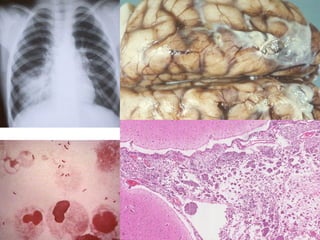

PCP

Methenamine SILVER

stain for

Pneumocystis carinii*

Pneumonia

HIV Patient • 30%to 40% of hospitalizations in HIV-infected individuals. • Bacterial pneumonias in HIV-infected persons are more common, more severe, and more often associated with bacteremia than in those without HIV infection. • The CD4+ T-cell count determines the risk of infection with specific organisms. – Bacterial and tubercular infections … more than 200 cells/mm3 – Pneumocystis pneumonia … less than 200 cells/mm3 – Cytomegalovirus, fungal, and Mycobacterium avium complex infections … less than 50 cells/mm3

• 54.

• 55.

• #52 * Really jiroveci, not carinii any more.

• #55 PCP is the most common pneumonia in AIDS patients. It is so prevalent, many rationales consist in giving treatment for it prophylactically. An interesting tidbit is that “cotton wool” or “wooly” exudates are described BOTH radiologically as well as histologically